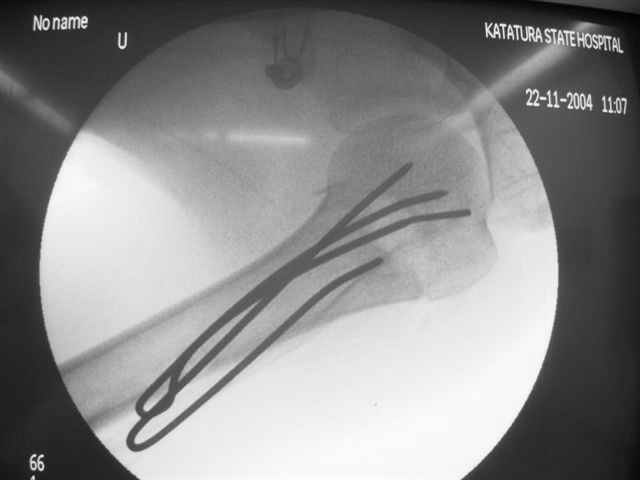

Коллеги, Больной прооперирован вчера. 19 летний пациент с переломом шейки плеча. Закрытая репозиция и чрескожная фиксация спицами под контролем ЭОПа ( техника проф. Лазарева)

Интраоперационный контроль на стабильность фиксации - сомнений в стабильности фиксации не возникло. Послеоперационный контроль сегодня......

Необходимость послеоперационного Рг контроля..... Больной запланирован на повторную манипуляцию и транспозицию спиц Евгений И Чекашкин